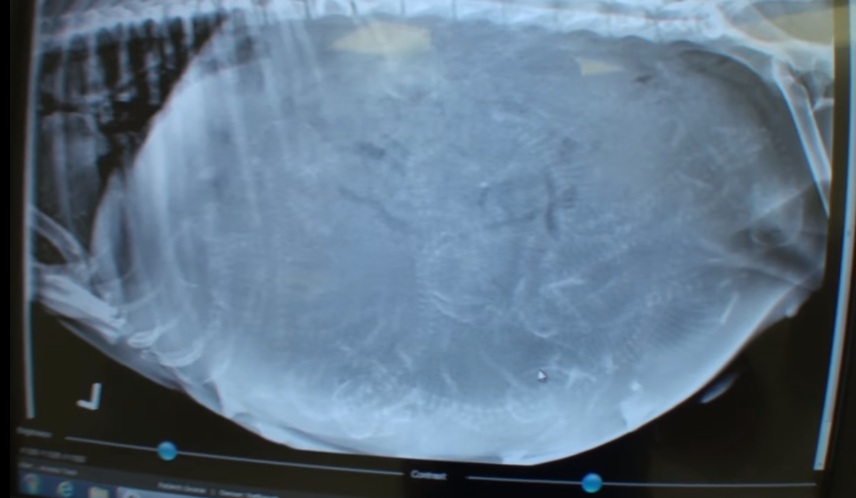

Gracie, the name given to her by her rescuers, who was sporting a big abdomen full of puppies is only about a year or 2 years of age. When she arrived at the clinic, they immediately had her X-ray taken to see how far her pregnancy is and if they can count how many pups were growing inside of her. However, the pups have not mineralized yet, which means they still have to wait for a few more weeks before they appear on the X-ray.

Dr. Matt has been keeping a close eye on the pregnant Gracie, and have patiently waited for the pups to show up on the x-ray so he’ll know how many pups are to be expected. Much to everyone’s surprise, a total number of 12 skeletons can be clearly seen and counted on Gracie’s X-ray. She is expected to deliver her pups in the next few days.